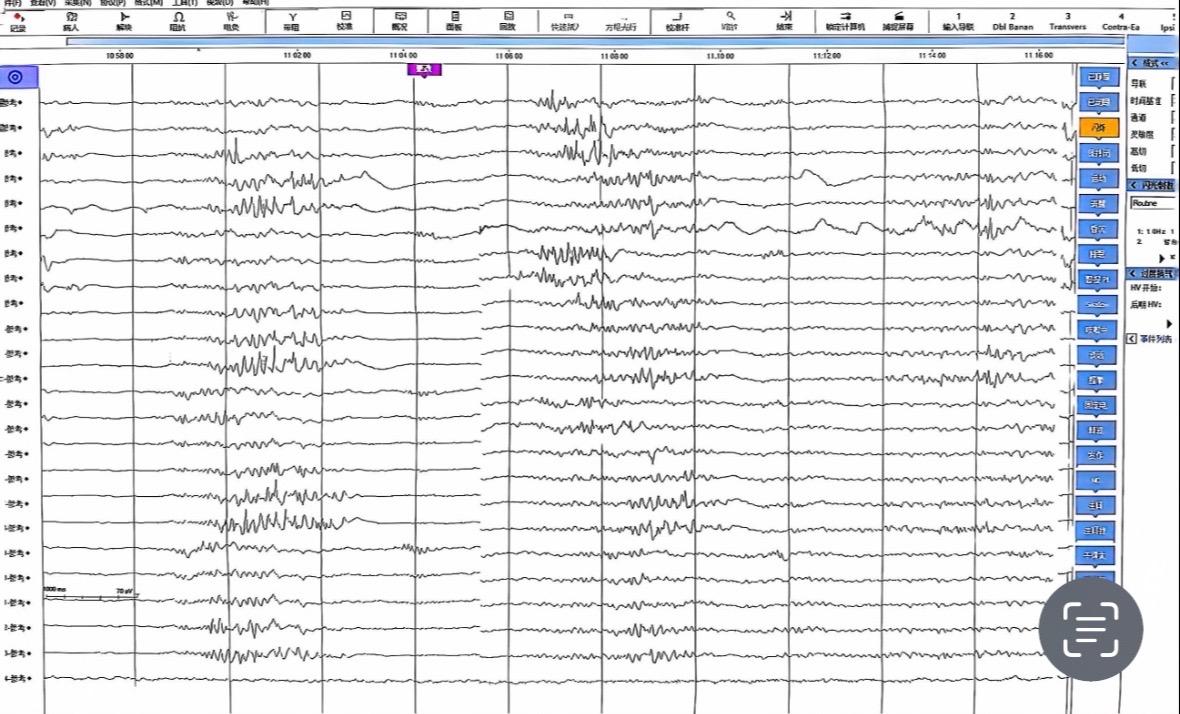

脑内血管瘤合并癫痫。其实海绵状血管瘤如果在非功能区手术难度一般,但是如果合并癫痫单纯切除海绵状血管瘤,术后还是可能发作,建议多手段联合,按癫痫来评估和手术,而非按肿物来评估,这和低级别胶质瘤并癫痫是一样的,单纯切除肿瘤的话癫痫控制可能不理想!